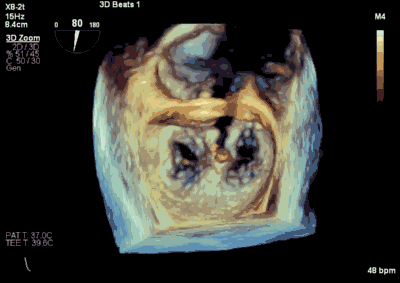

王焱、王斌教授团队通过术前和台北荣民总医院(Taipei Veterans General Hospital)宋思贤教授进行了详细的讨论并制定了最优的手术策略,同时术中视频连线获得宋思贤教授的技术支持,国产自拍 超声内科苏茂龙教授负责术中超声心动图引导。患者全麻以后,在经食道超声心动图和X射线引导下,经股静脉入路,将MitraClip瓣膜夹顺利送至二尖瓣前后叶交界中心处,成功捕捉二尖瓣前叶A2和后叶P2,经超声心动图反复确认瓣叶夹持牢固后,测定有效夹持长度11mm,评估反流量降至微量,释放瓣膜夹,超声心动图评估瓣膜夹位置和功能良好,测定左房压降至11/6mmHg,再次评估反流量仍为微量,手术顺利完成。

▲ 术后超声检查显示轻度二尖瓣反流

▲ MitraClip释放